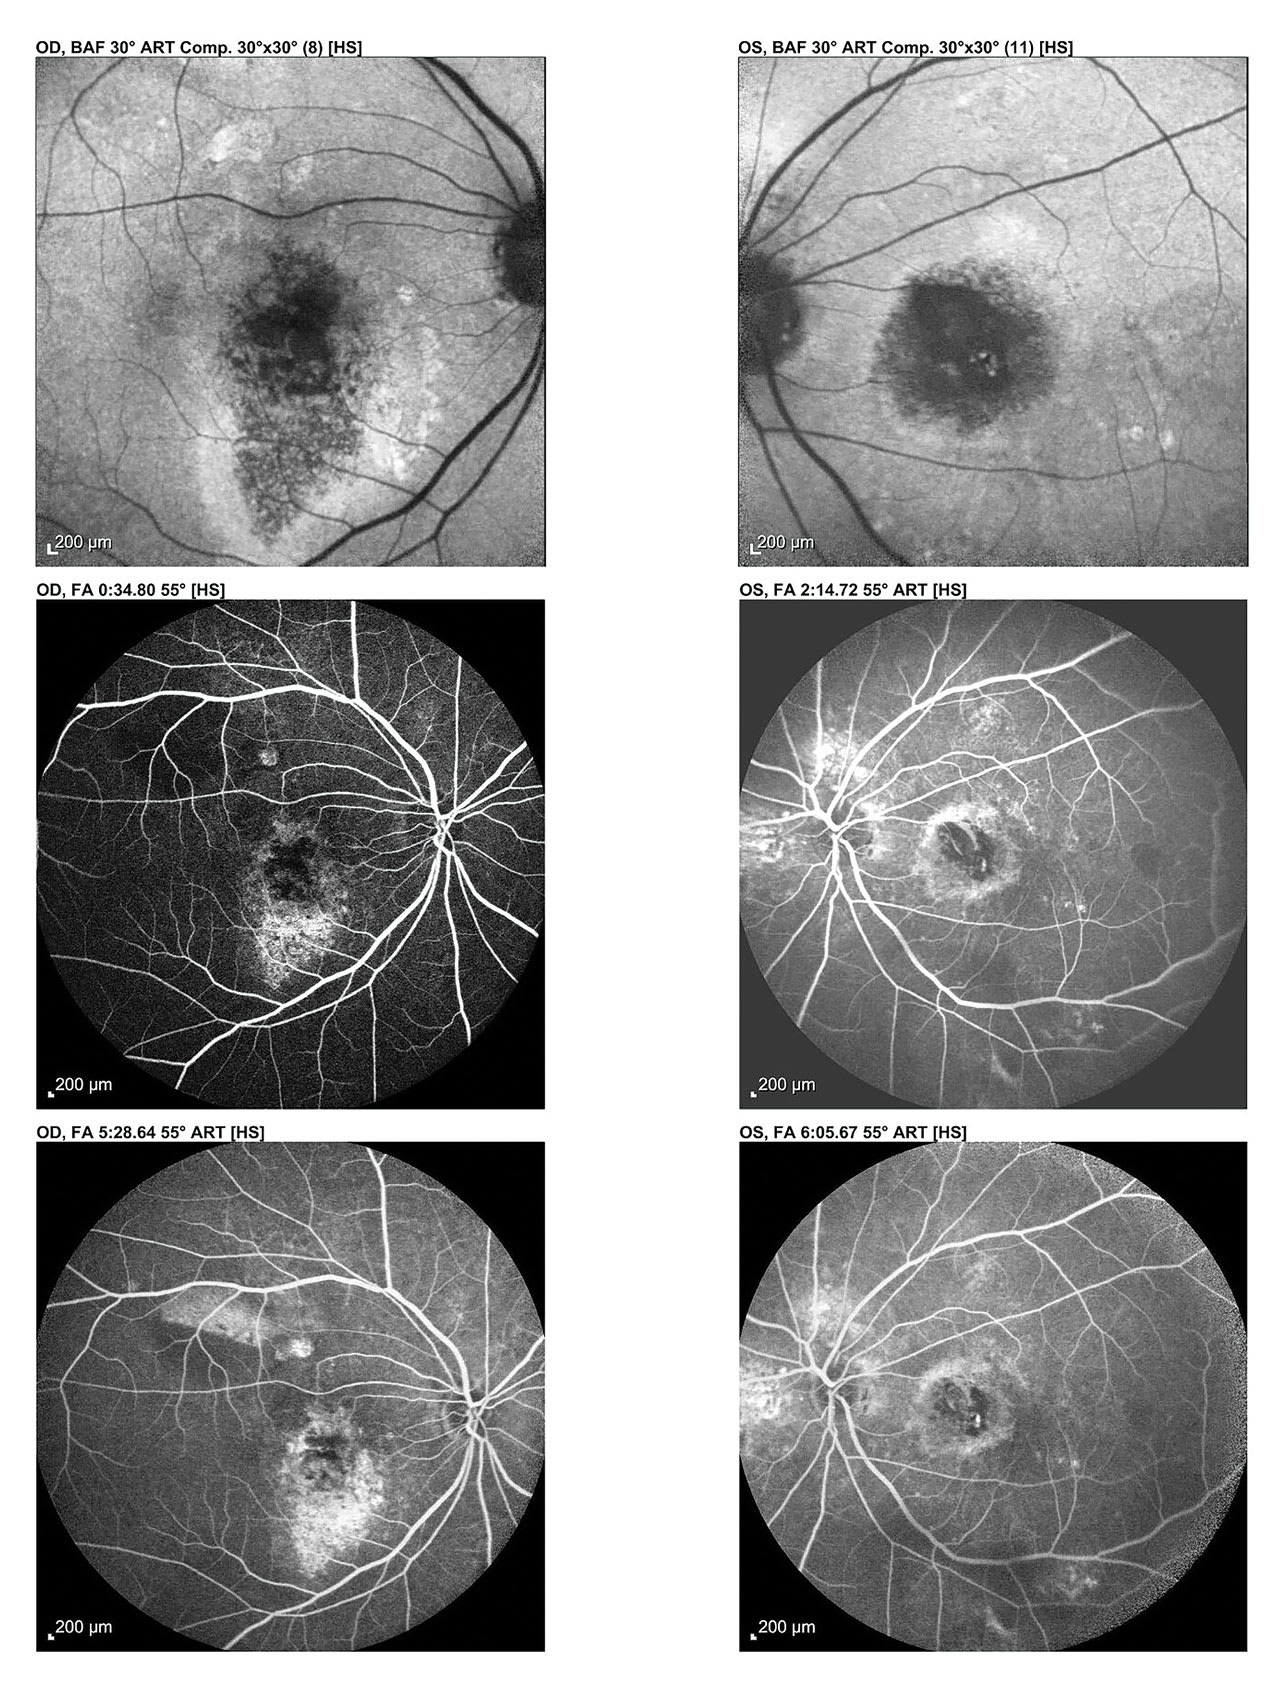

Fluorescein Angiography

Fluorescein angiography (FA) is used to detect and characterize choroidal neovascularization (CNV) in neovascular AMD.5 The intravenous injection of fluorescein dye and sequential imaging enables the OD to identify retinal leakage, staining, and pooling.

Patient-centered explanation: “This test helps me see how your blood flows to your retina, and whether all the areas of the retina are getting as much blood as they should, or if there are areas of new growth of blood vessels.”

Fundus Autofluorescence (FAF)

This uses specific light wavelengths to cause natural retinal pigments in the RPE to fluoresce.8 Areas of increased fluorescence indicate stress. Dark areas indicate RPE atrophy. FAF is particularly helpful for detecting GA and in providing patient education: patients can often intuitively understand these images.

Patient-centered explanation: “This scan uses light to highlight areas of stress or damage in the retina’s pigment layer before they appear in regular photos. Bright areas might indicate too much waste build-up, and dark areas may indicate retinal damage.”